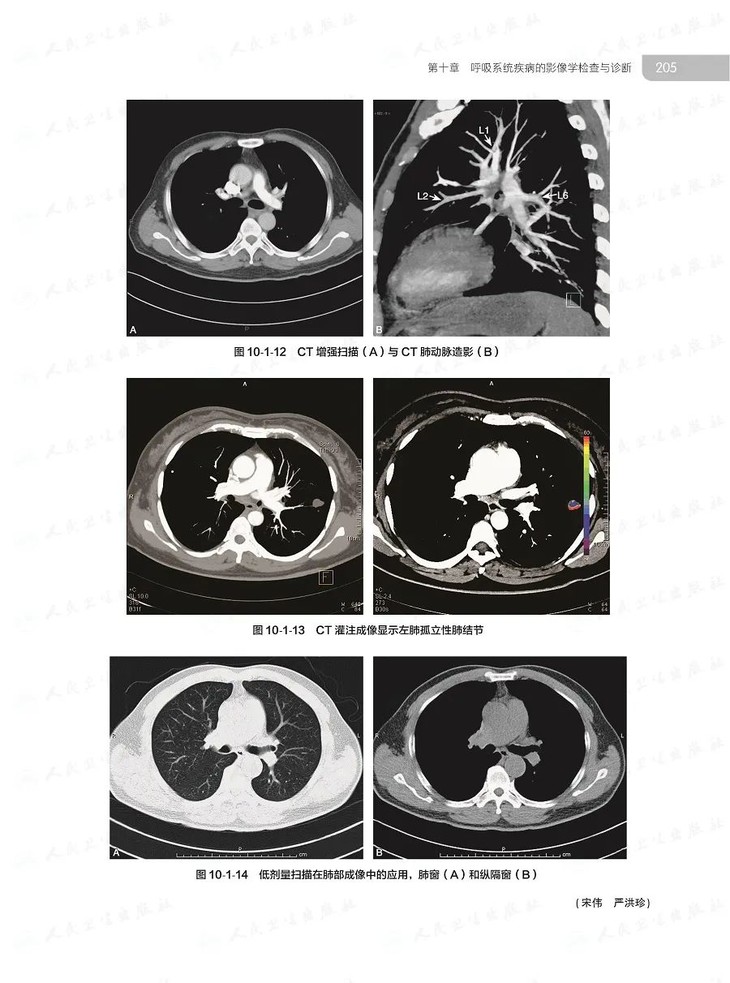

本书共4篇43章,316万字,萃取我国殿堂级呼吸医学专家的临床思维和诊治经验,对我国呼吸病学领域的基本理论技术及先进的临床实践和科研成果等进行了系统阐述,将国际临床新进展、诊治新技术、新指南标准等加以总结,较全面地反映了国内外呼吸病学的发展水平,基础与临床紧密结合,内容精准实用,配以丰富精美图片,是中国PCCM医生必备的案头工具书。